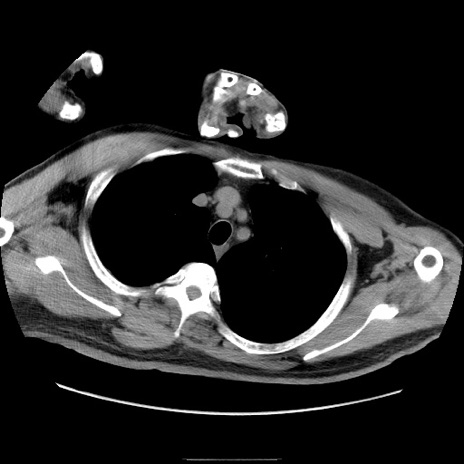

症例22(横断像)

【症例】50歳代男性

【主訴】腹痛

【現病歴】AVMからの被殻出血のため回復期リハ病棟入院中。 本日午後3時頃急に下腹部痛が出現した。

【既往歴】AVM、被殻出血、虫垂炎、高血圧

【身体所見】意識晴明、左半身不全麻痺、会話の理解は良好、36.5°C、腹部:膨隆、全体に板状硬、下腹部正中に圧痛点あり、反跳痛-、筋性防御不明、右下腹部にope scar

【データ】WBC 9400、CRP 0.06